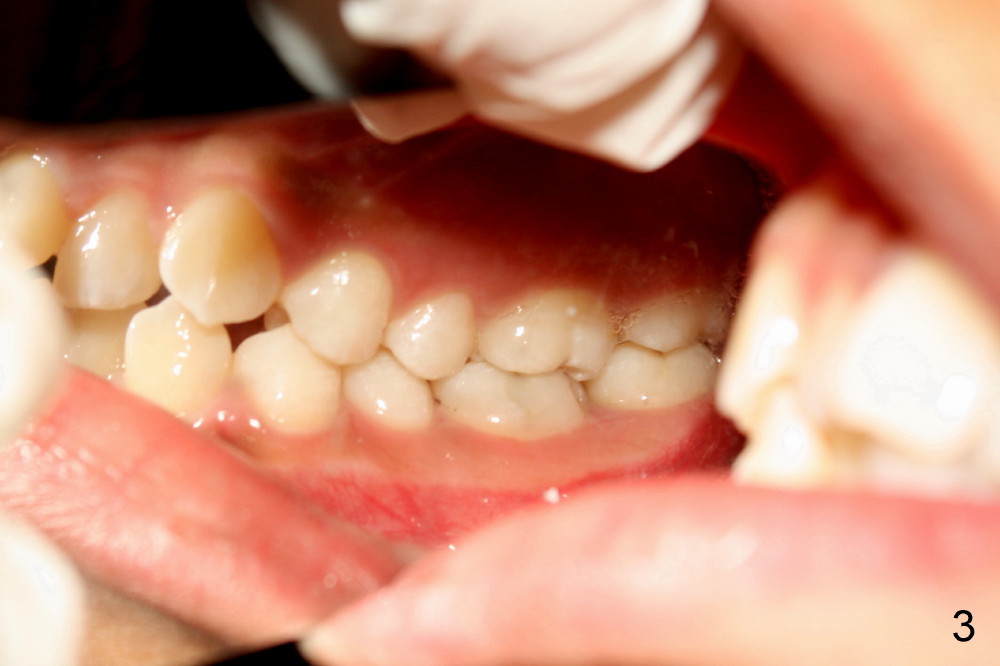

There is basically Class I occlusion in molar and canine regions bilaterally (Fig.3,5). Crowding is severe in the anterior area (Fig.4).

Banding and bracketing was finished with installation of .012 niti wires on August 12, 2013. Each visit, the next thicker and stiffer wires will be changed if there is not much tension until .016x.016 wires. Surgical exposure of #15 will be performed. The tooth will be retracted for eruption using the upper rectangular wire as an anchorage orthodontically.